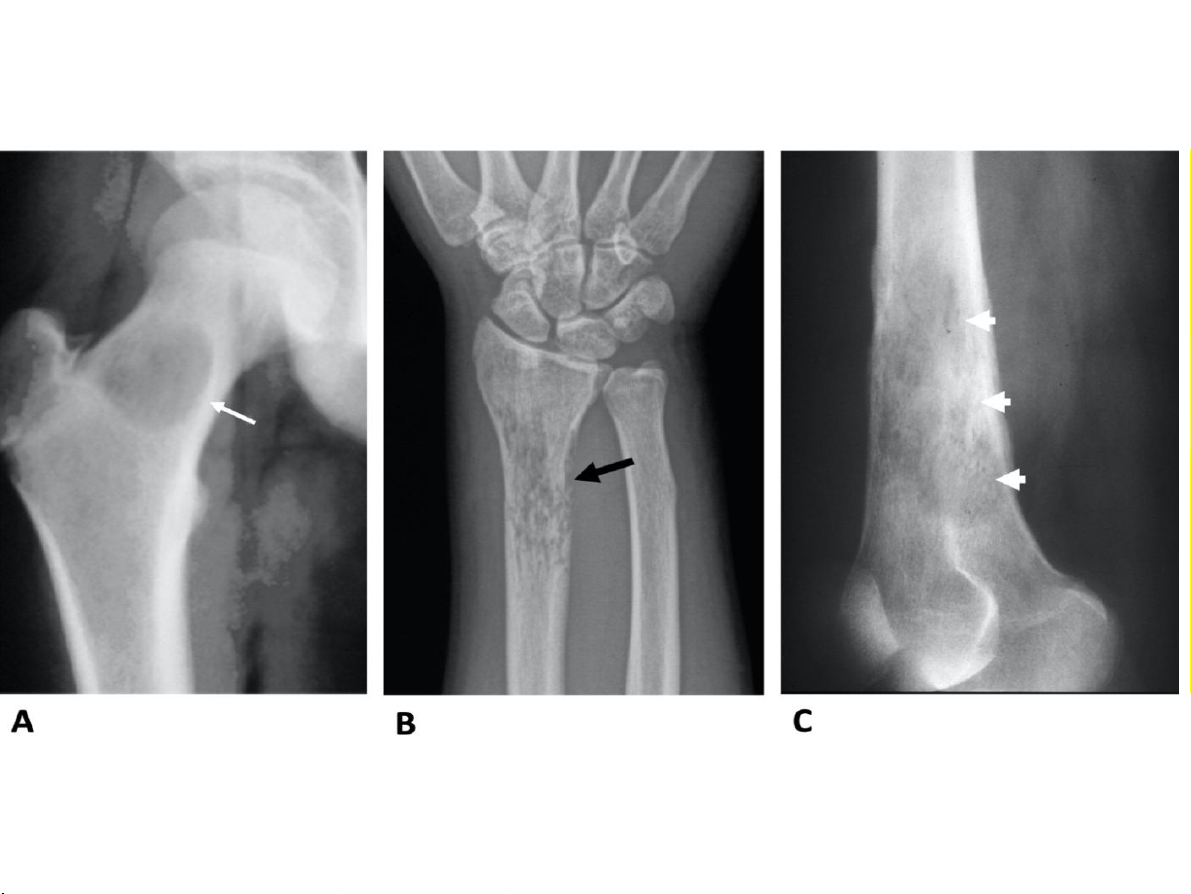

Bất thường về cấu trúc Huỷ xương 1.Giới hạn tổn thương 2.Phá huỷ vỏ xương: tổn thương ác tính? 31-Jan-23 CĐHA Cơ-Xương-Khớp

Vỏ xương: liên tục? Bị phá huỷ? Huỷ xương 1.Giới hạn tổn thương

1.Phá huỷ vỏ xương ác tính? 31-Jan-23 CĐHA Cơ-Xương-Khớp 31-Jan-23 CĐHA Cơ-Xương-Khớp 31-Jan-23 CĐHA Cơ-Xương-Khớp